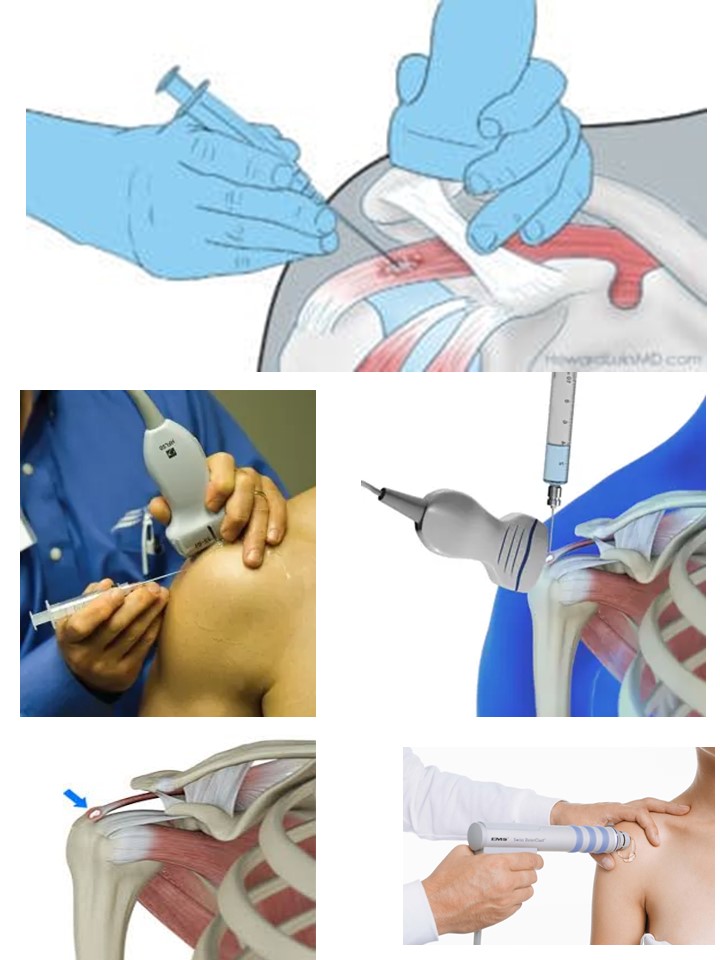

#ကုသခြင်း

အခြားရောဂါများ ဖေါ်ထုတ်ရင်း အကြောအဆစ် အချို့အစိတ်အပိုင်းများတွင် အမှတ်မထင် ကျောက်များတွေ့လေ့ရှိသော်လည်း ပြသနာမပေးလျှင် ကုသစရာမလိုတတ်ပါ။ နာကျင်ရောင်ရမ်း ပြသနာ ပေးသော ကျောက်များကို ကုသရာ၌ အကိုက်အခဲပျောက်ဆေးသောက်ခြင်း၊ ကာယကုထုံး physiotherapy များကလည်း သက်သာစေနိုင်ပါသည်။ ကာယကုဠာနများ၌ Extra corporal Shock wave ဟုခေါ်သော စက်များဖြင့် ကျောက်များကို Shock တိုက်လိုက်ခြင်းကလည်း ကျောက်ချေရာ၌ အကူညီရစေပြီး ထိရောက်ပါသည်။ တယ်လီဗွီးရှင်း ဓါတ်မှန်အကူအညီဖြင့် ကျောက်အား ဆေးထိုးအပ်ဖြင့် ထိုးခွဲချေ၍ စုတ်ထုတ်ကာ ဆေးထိုးကုသခြင်းကလည်း သုတေသနများအရ ထိရောက်ကောင်းမွန်သည်ဟု အဖြေများ တွေ့ရပါသည်။ စတီးရိုက် အရောင်ကျဆေး အား ကျောက်အနီး ထိုးခြင်းကလည်း သက်သာ စေနိုင် ပါသည်။ ခွဲစိတ် ကျောက်ထုတ်ခြင်းနှင့်လည်းကုသကြပါသည်။နာကျင်မှုစလာလျှင် ဘာရောဂါလည်းသေချာအောင် ကျန်းမာရေးပညာရှင်များနှင့် တိုင်ပင်ပါ၊ အချို့ ရောဂါသေးလေးတွေကတော့ ရေခဲကပ်၊ အကိုက်အခဲပျောက်ဆေးသောက်၊ အနားပေးလျင် သက်သာ သွားတတ်ပါသည်။